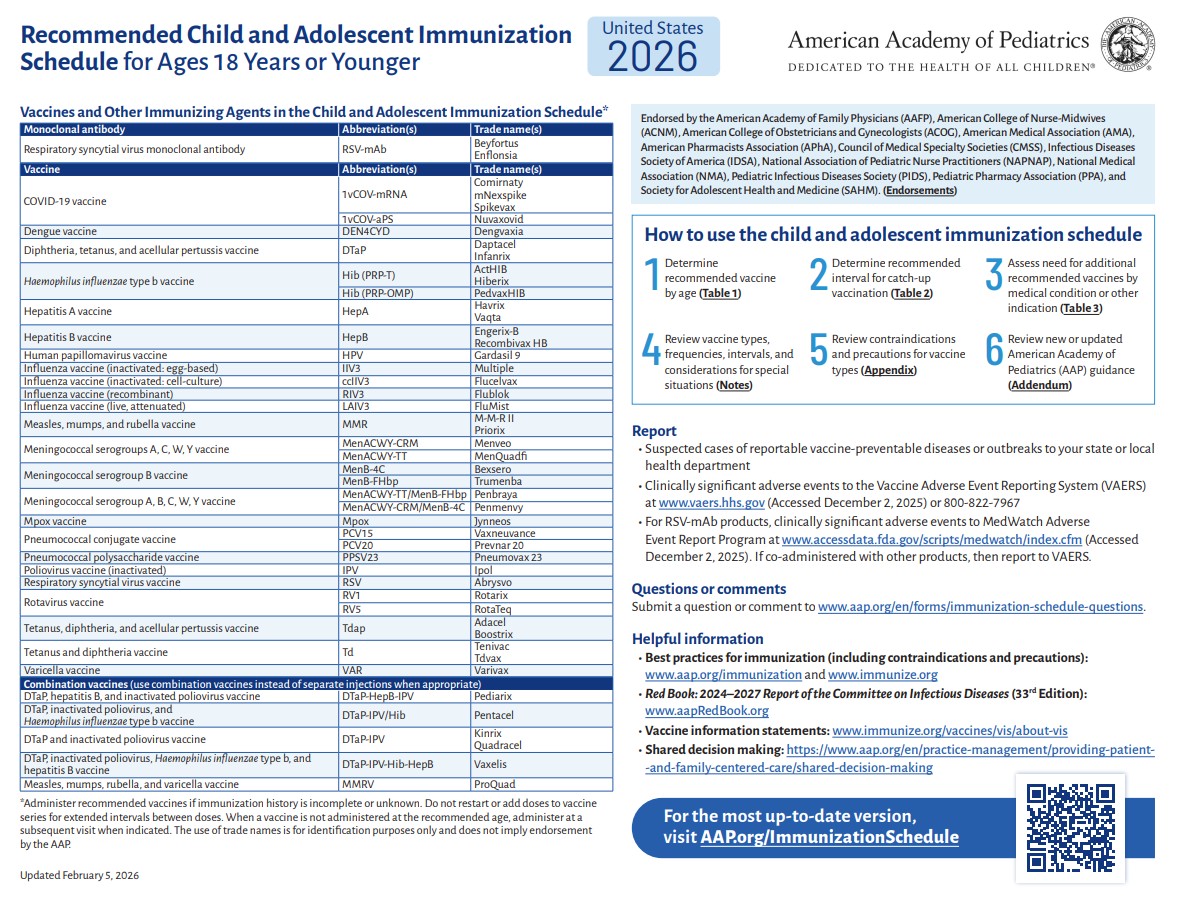

p 1